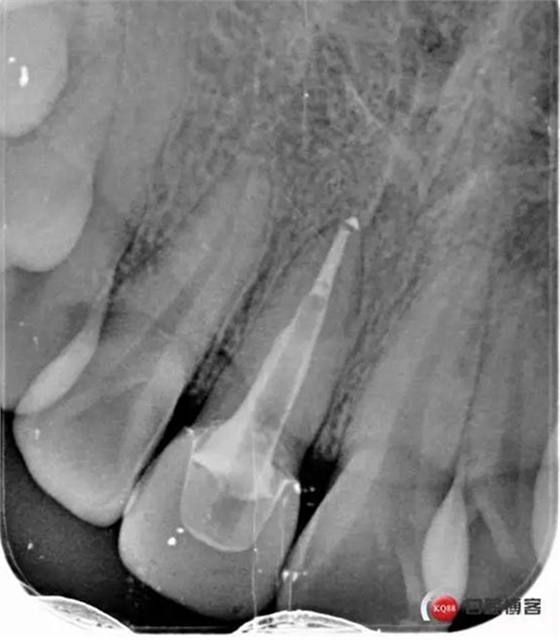

看起來有點(diǎn)頭痛哈,拍片檢查

牙根長度比較號(hào),根充完善。這張片子也可以看出,為什么上次脫落了,樁的深度不夠,而且明顯樁根樁道不匹配,打的樁都沒有到位。

術(shù)后牙片可以看出樁的長度有明顯增加。到達(dá)預(yù)備長度。術(shù)后齦緣高度與鄰牙一致